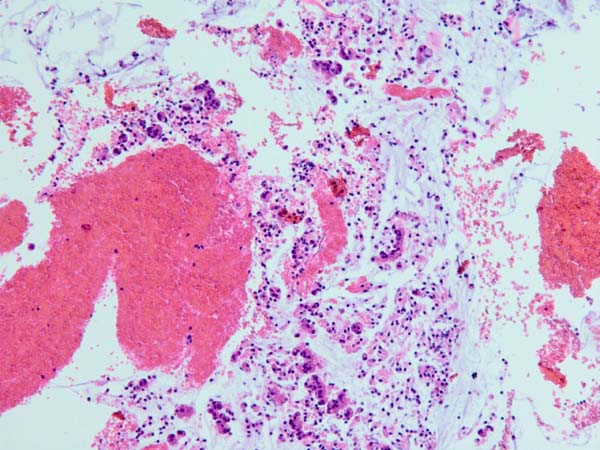

ワンちゃんが乳腺にできた複数のシコリを気にされて来院されました。bilateral mastectomyで対応しました。摘出後の病理組織検査の結果は、「R3-4間腫瘤:乳腺癌(複合型)」でそれ以外は「良性乳腺混合腫瘍」でした。無事元気に退院し、その後再発もなく経過は良好です。よかったね。